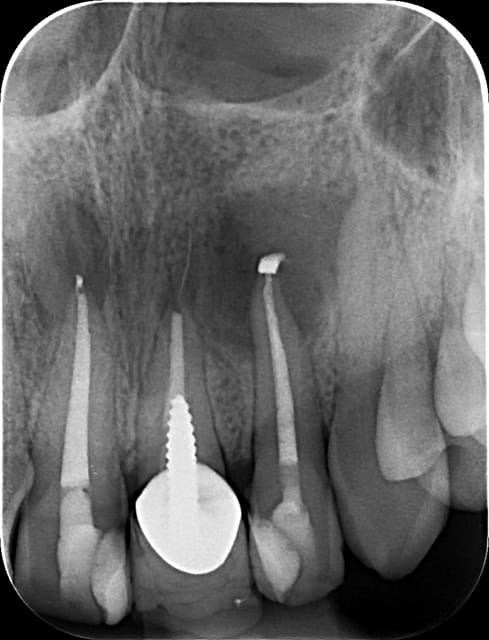

Apres obturation - fig.3,4

Apres 8 mois

Fig.5,6